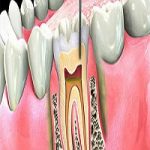

Dental implants are the ideal teeth replacement solution for patients missing one, some, or all of their teeth. Sunny Dental provides all-on-4, same-day implants in Sunny Isles Beach, FL.

Dental implants are the ideal teeth replacement solution for patients missing one, some, or all of their teeth. Sunny Dental provides all-on-4, same-day implants in Sunny Isles Beach, FL.